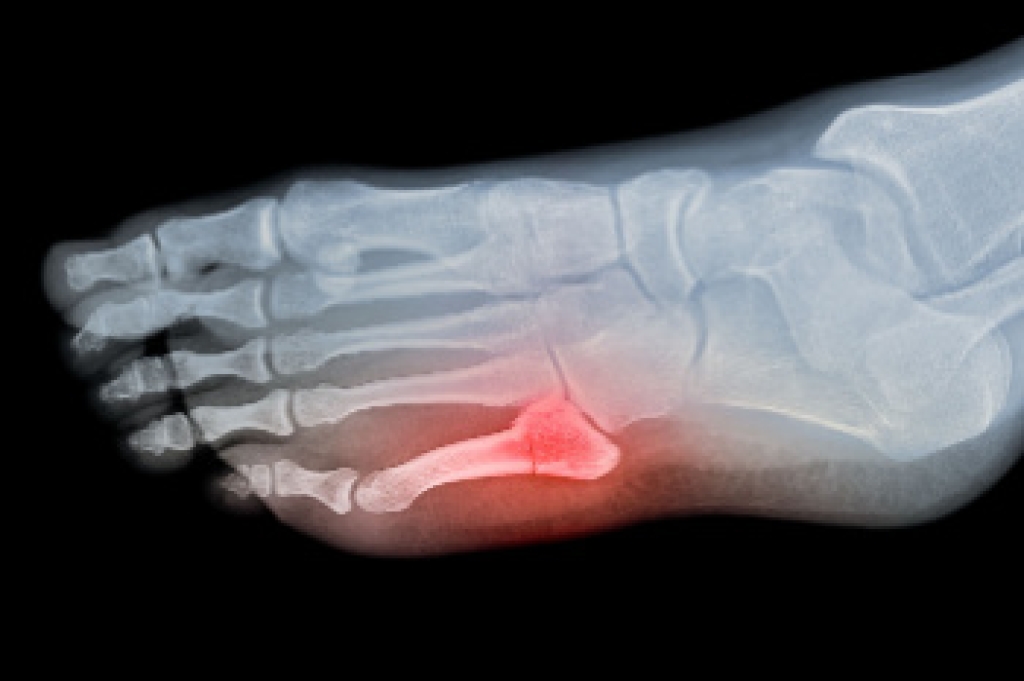

Gout is a form of arthritis that is characterized by sudden, severe attacks of pain, redness, and tenderness in the joints. The condition usually affects the joint at the base of the big toe. A gout attack can occur at any random time, such as the middle of the night while you are asleep.

- Intense Joint Pain - Usually around the large joint of your big toe, and it most severe within the first four to twelve hours

- Inflammation and Redness -Affected joints may become swollen, tender, warm and red